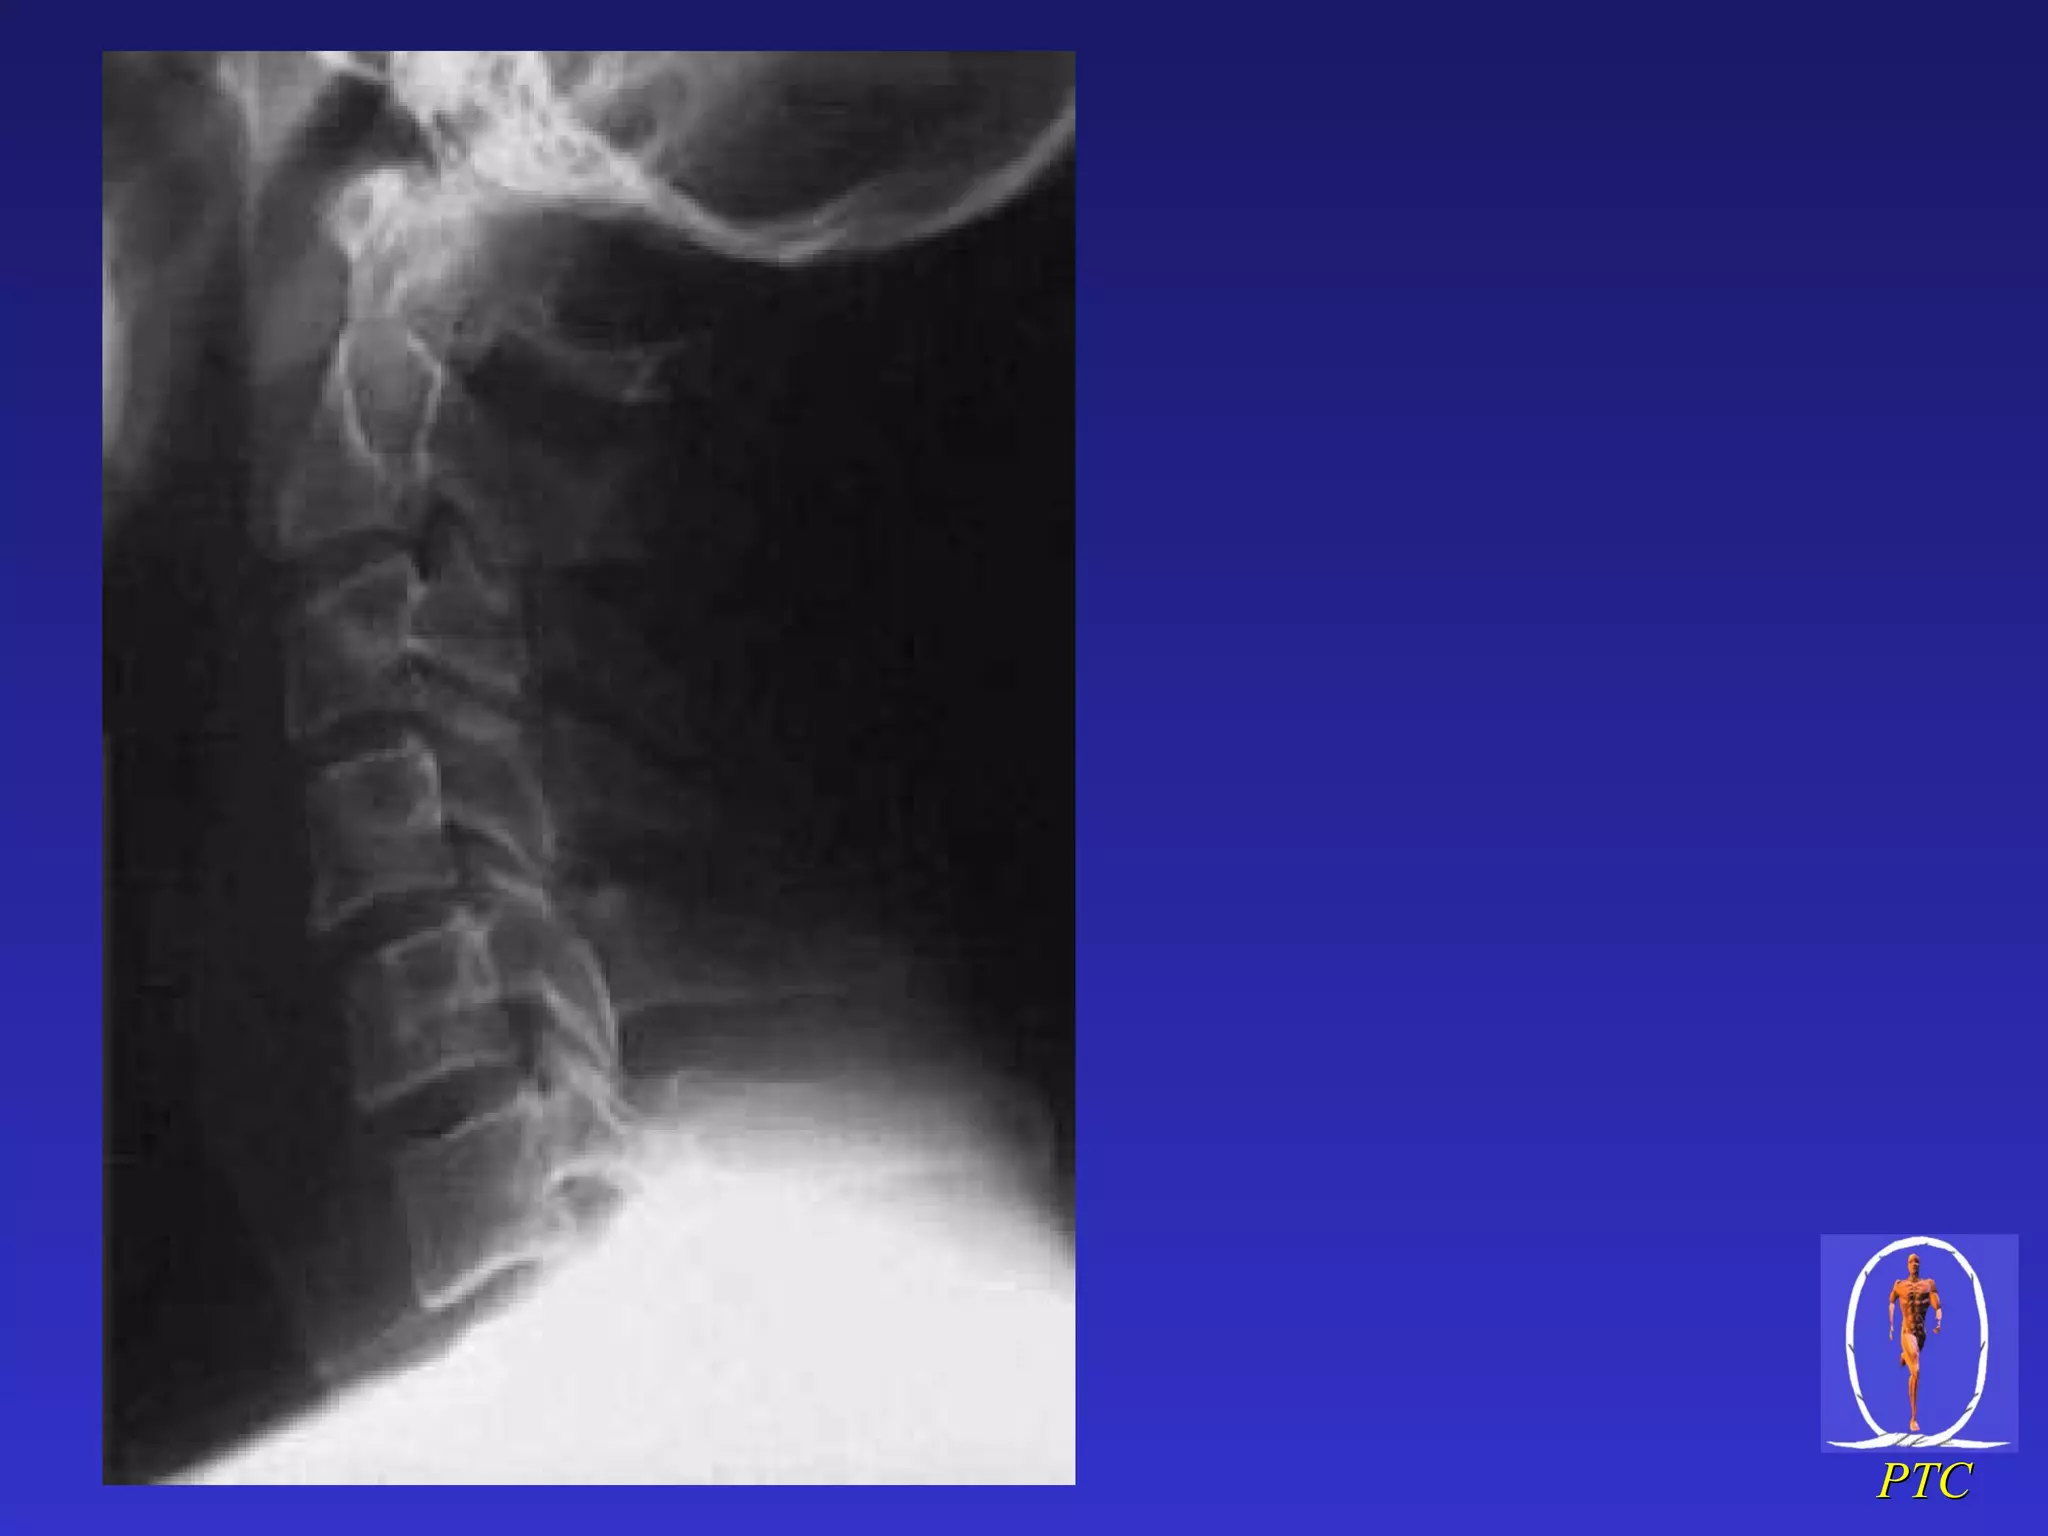

C/ spine  x-rays – lat view Identify Occipital condyles All seven cervical vertebrae Superior aspect of body of T1 Anatomic assessment Alignment – 5 lordotic curves Bones – contour Cartilage – discs and facet joints Soft tissues – pre-vertebral and inter-spinous space, ADI OC T1